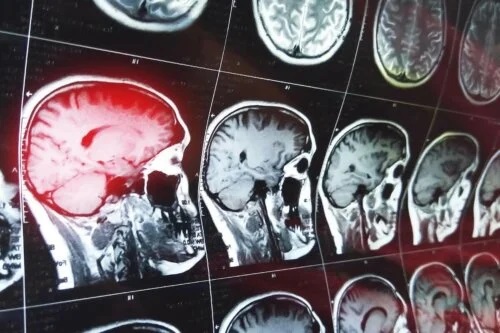

Cauzele defecțiunilor de memorie care produc confabulații la pacienți sunt rezultatul deteriorării zonei frontale a creierului. Zona afectată este zona anterioară bazală, unde se află zonele orbitofrontale și ventromediale.